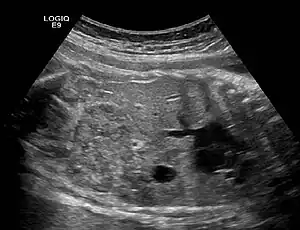

Ectopic crossed fused kidney in a fetus approx. 34 weeks

Crossed dystopia (syn.unilateral fusion cross fused renal ectopia) is a rare form of renal ectopia where both kidneys are on the same side of the spine.[1] In many cases, the two kidneys are fused together, yet retain their own vessels and ureters.[2] The ureter of the lower kidney crosses the midline to enter the bladder on the contralateral side. Both renal pelves can lie one above each other medial to the renal parenchyma (unilateral long kidney) or the pelvis of the crossed kidney faces laterally (unilateral S-shaped kidney). Urogram is diagnostic.

The anomaly can be diagnosed through ultrasound or urography, but surgical intervention is only necessary if there are other complications, such as tumors or pyelonephritis.